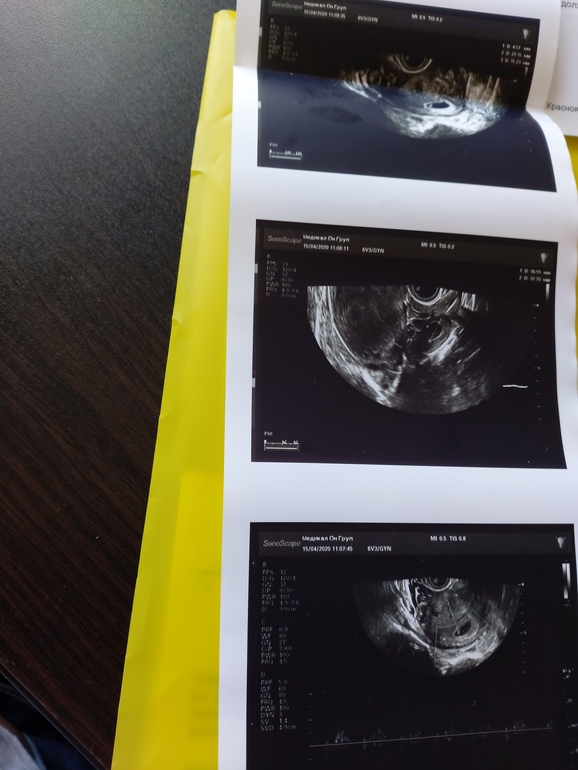

УЗИ, КТГ, доплерДевочки сегодня была на узи, слава богу нашли эмбриончика и сердцебиение! Но появились некоторые вопросы... На узи поставили угрозу и ретрохориальную гематому (к слову болей и выделений у меня ттт нет) Во втором узи написали: Плодное яйцо 30*15.2 мм ктр 4.6 мм, желточный мешок 4.2 мм. На границе с шейкой ретрохориальная гематома 27.3*14.5 мм Правый яичник:в скане анэхогенное образование размерами 16*13ммД, внутреннее содержимое однородное. Заключение; беременность 5-6 нед Гипертонус матки по передней стенке. Эхокартина ретрохориальной гематомы. Ретенционное образование правого яичника (желтое тело) А теперь внимание вопросы на первом узи желтое тело было в левом яичнике до 19 мм А теперь уже в правом яичнике желтое тело. Такое возможно? еще про анэхогенное образование написали...Первое узи если что есть у меня в дневнике. Хотела на хгч сегодня сбегать, да не успела...да и что оно сейчас уже покажет.. Вот сейчас меня смущает эта гематома и желтое тело в обоих яичниках. Может ли в данной ситуации быть многоплодная беременность? Читала что у некоторых девчонок на малом сроке ставили ратрохориальную гематому а в 12 нед узнавали о многоплодной беременности.

Ниже прикреплю узи.

![]()